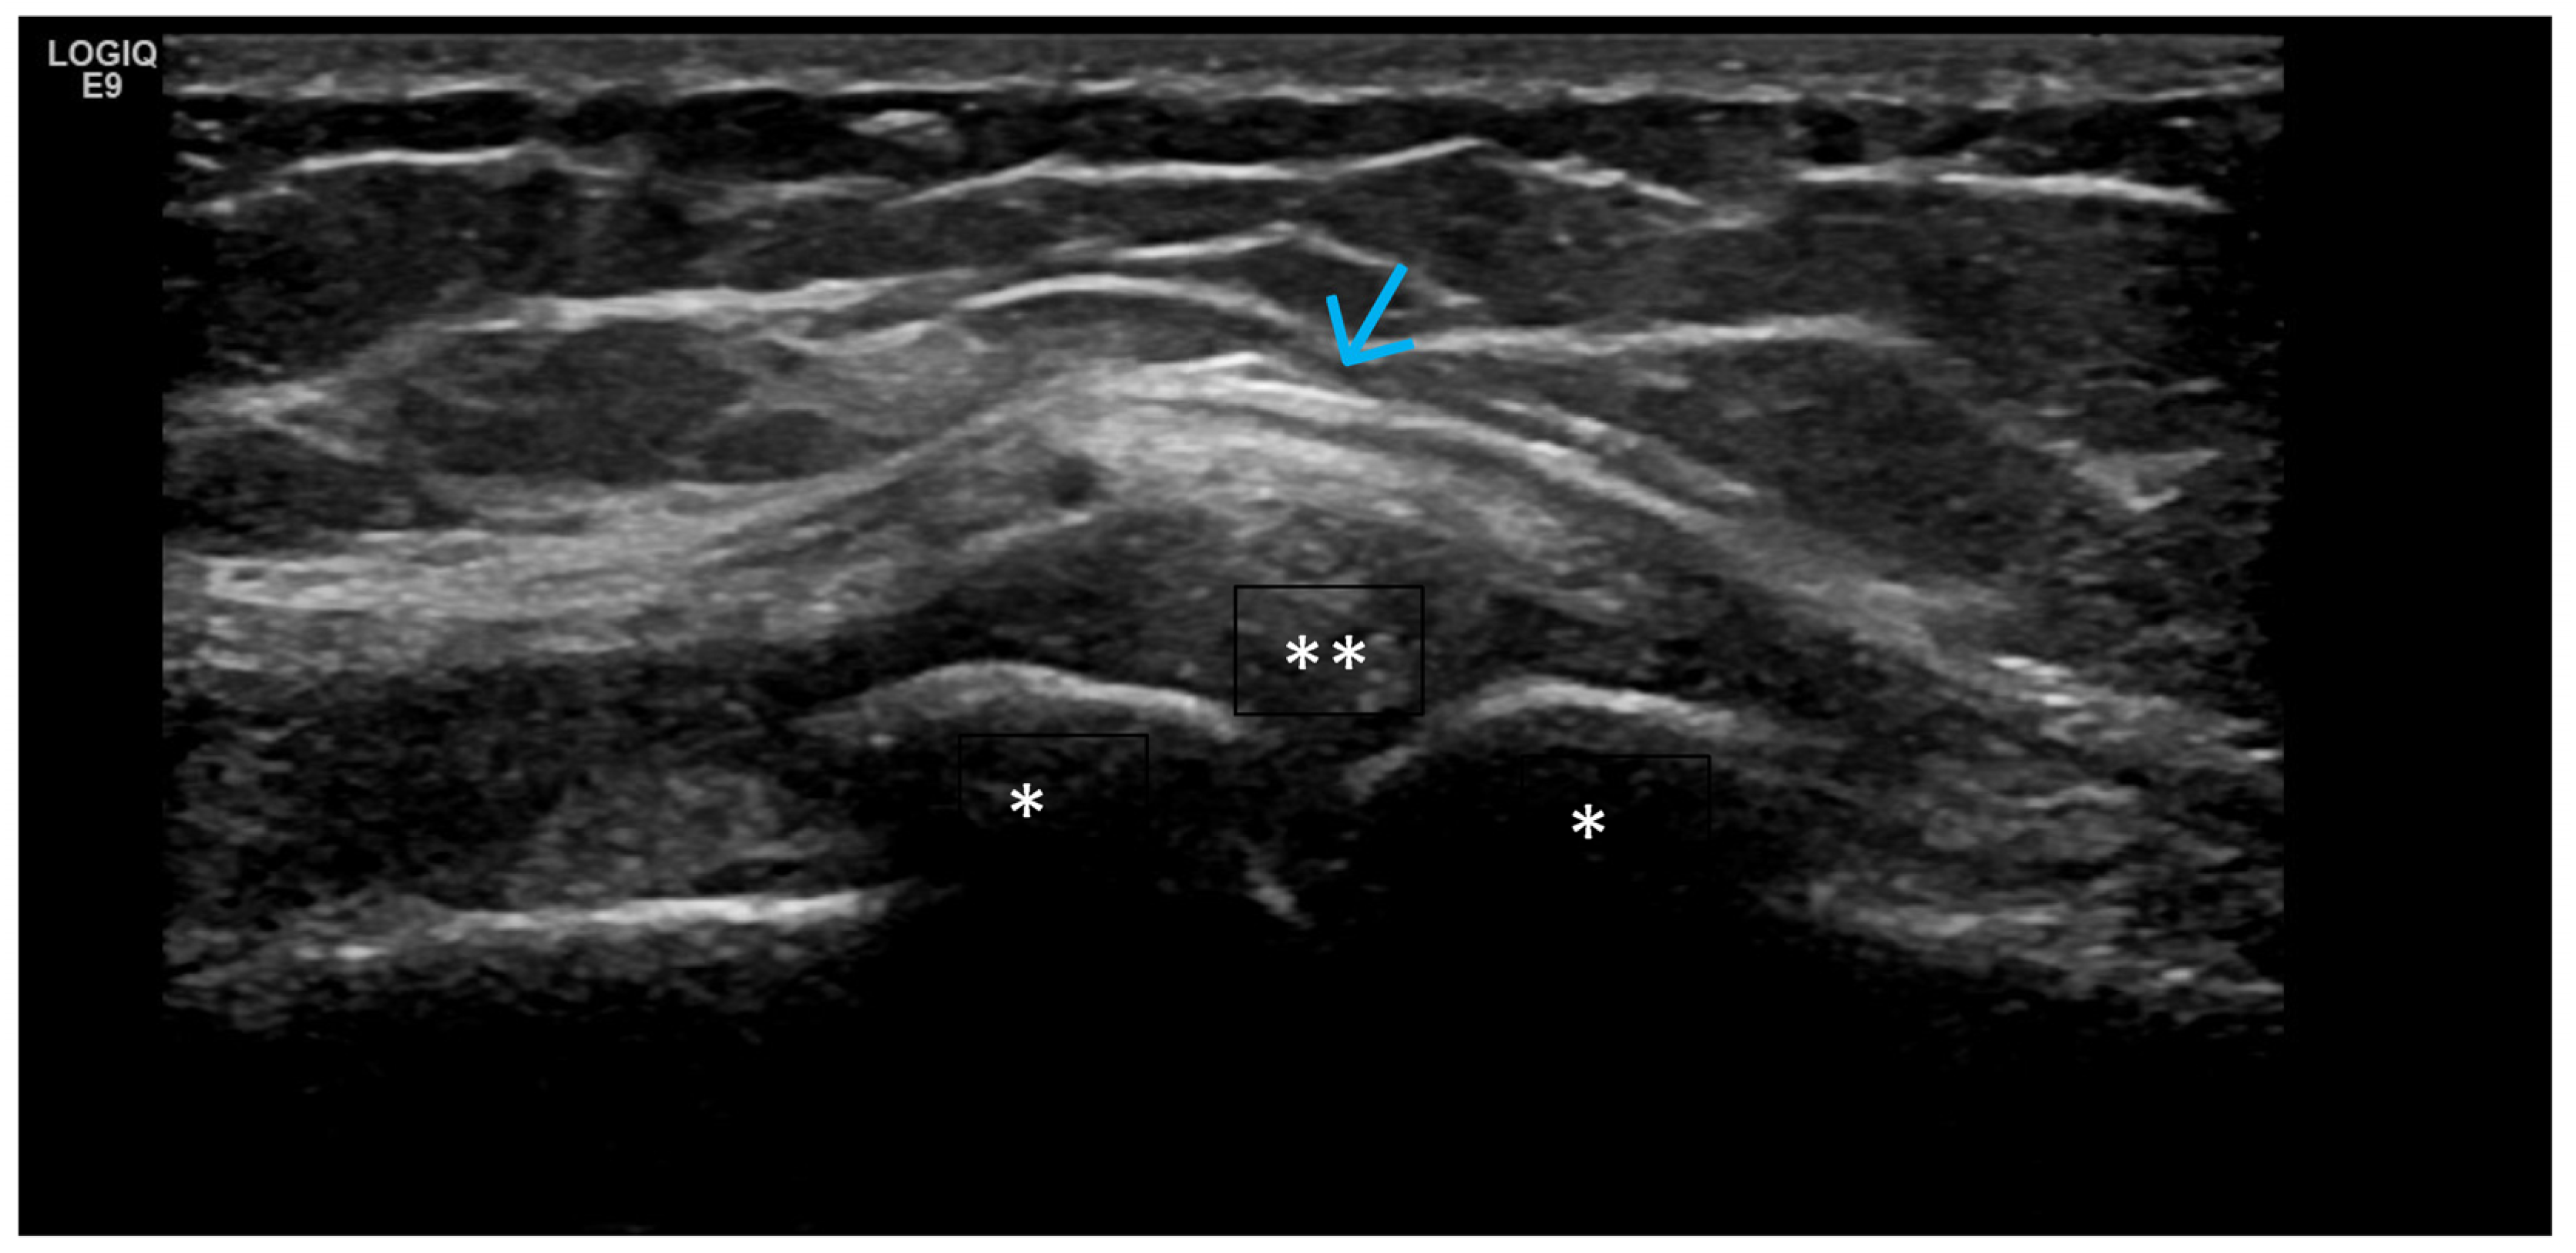

4. Examples of US Phenotypes